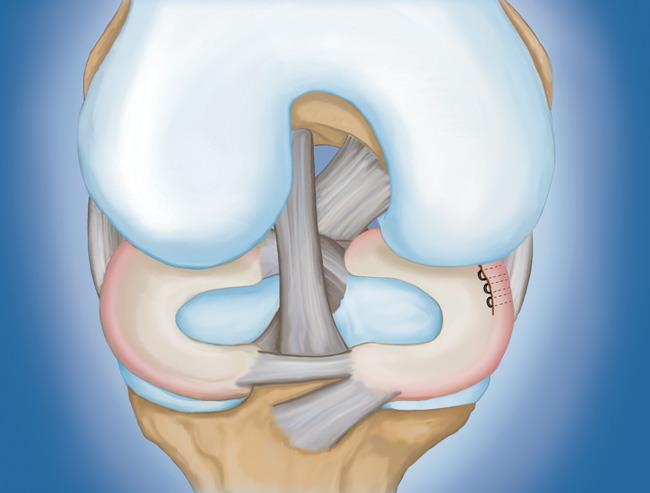

- 半月板修復(fù)。 一些半月板撕裂可以通過將撕裂的碎片縫合(縫合)在一起來修復(fù)。撕裂能否成功修復(fù)取決于撕裂的類型,以及受傷半月板的整體狀況。因?yàn)榘朐掳灞仨氁黄鹩希迯?fù)的恢復(fù)時(shí)間比半月板切除術(shù)長。

初步愈合完成后,您的醫(yī)生將進(jìn)行康復(fù)鍛煉。定期鍛煉以恢復(fù)膝關(guān)節(jié)的靈活性和力量是必要的。您將從鍛煉開始,以改善您的運(yùn)動(dòng)范圍。力量訓(xùn)練將逐漸添加到您的康復(fù)計(jì)劃中。

在許多情況下,康復(fù)可以在家中進(jìn)行,但您的醫(yī)生可能會(huì)建議您與物理治療師一起工作。半月板修復(fù)的康復(fù)時(shí)間約為3至6個(gè)月。半月板切除術(shù)需要更少的愈合時(shí)間——大約3到6周。